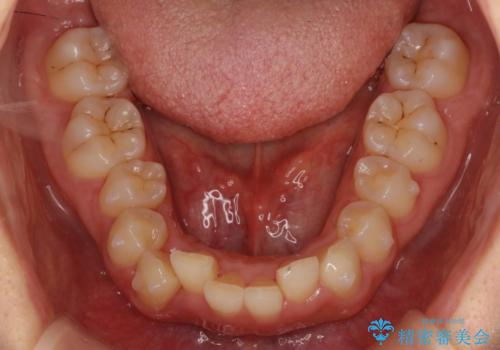

- 前歯のがたがたと出っ歯を主訴に来院。

CTを撮影したところ、臼歯部の頬側の骨の厚みが非常に大きく、通常では考えられない量の歯列の拡大が可能でした。

今回は健康を損なわずに非抜歯で治療が可能でしたが、

歯ぐきや骨の厚みが薄い他の患者さんでは難しいです。

左上5は180度捻転していましたので、そのまま並べています。

遠心移動などは行わず、IPRと拡大のみで治療を行いました。